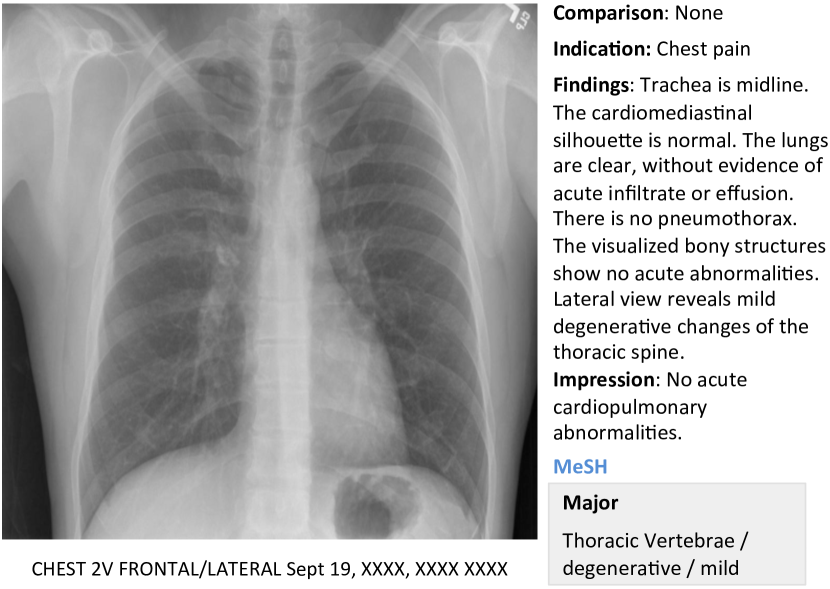

In this work, we demonstrate how to automatically annotate chest x-rays with diseases along with describing the contexts of a disease, e.g., location, severity, and the affected organs. A publicly available radiology dataset is exploited which contains chest x-ray images and reports published on the Web as a part of the OpenI [2] open source literature and biomedical image collections. An example of a chest x-ray image, report, and annotations available on OpenI is shown in Figure 1.

We use a publicly available radiology dataset of chest x-rays and reports that is a subset of the OpenI [2] open source literature and biomedical image collections. It contains 3,955 radiology reports from the Indiana Network for Patient Care, and 7,470 associated chest x-rays from the hospitals’ picture archiving systems. The entire dataset has been fully anonymized via an aggressive anonymization scheme, which achieved 100% precision in de-identification. However, a few findings have been rendered uninterpretable. More details about the dataset and the anonymization procedure can be found in [11], and an example case of the dataset is shown in Figure 1.

Each report is structured as comparison, indication, findings, and impression sections, in line with a common radiology reporting format for diagnostic chest x-rays. In the example shown in Figure 1, we observe an error resulting from the aggressive automated de-identification scheme. A word possibly indicating a disease was falsely detected as a personal information, and was thereby “anonymized” as “XXXX”. While radiology reports contain comprehensive information about the image and the patient, they may also contain information that cannot be inferred from the image content. For instance, in the example shown in Figure 1, it is probably impossible to determine that the image is of a Burmese male.

More examples of chest x-ray image, report, and annotations available on OpenI [2] is shown in Figure 7.